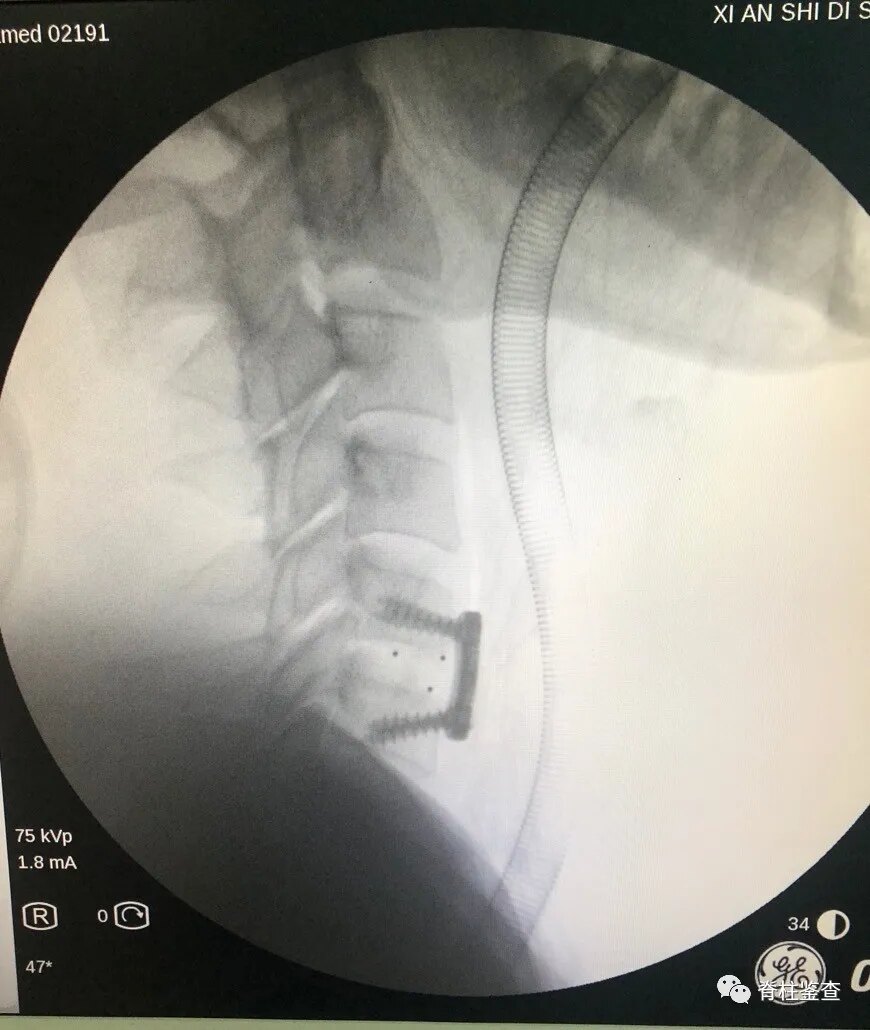

神经脊柱外科 满月 常见脊柱手术病例分享 颈椎病 颈椎病